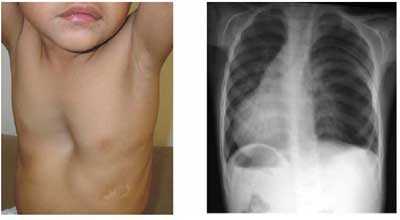

Π‘ΠΈΠ»ΡΠ½Π°Ρ ΠΎΠ΄ΡΡΠΊΠ° Π²ΠΏΠ»ΠΎΡΡ Π΄ΠΎ ΡΠ΄ΡΡΠ΅Π½ΠΈΡ, ΡΠ°ΡΡΠΈΡΠ΅Π½ΠΈΠ΅ ΠΌΠ΅ΠΆΡΠ΅Π±Π΅ΡΠ½ΡΡ ΠΏΡΠΎΠΌΠ΅ΠΆΡΡΠΊΠΎΠ², Π±ΠΎΡΠΊΠΎΠΎΠ±ΡΠ°Π·Π½Π°Ρ Π³ΡΡΠ΄Π½Π°Ρ ΠΊΠ»Π΅ΡΠΊΠ°, ΠΎΡΠ»Π°Π±Π»Π΅Π½Π½ΠΎΠ΅ Π΄ΡΡ Π°Π½ΠΈΠ΅, ΡΠΌΠ΅Π½ΡΡΠ΅Π½ΠΈΠ΅ ΠΏΠΎΠ΄Π²ΠΈΠΆΠ½ΠΎΡΡΠΈ Π΄ΠΈΠ°ΡΡΠ°Π³ΠΌΡ, ΠΏΠΎΠ²ΡΡΠ΅Π½ΠΈΠ΅ ΠΏΡΠΎΠ·ΡΠ°ΡΠ½ΠΎΡΡΠΈ Π»Π΅Π³ΠΎΡΠ½ΡΡ ΠΏΠΎΠ»Π΅ΠΉ ΠΏΡΠΈ ΡΠ΅Π½ΡΠ³Π΅Π½ΠΎΠ»ΠΎΠ³ΠΈΡΠ΅ΡΠΊΠΎΠΌ ΠΈΡΡΠ»Π΅Π΄ΠΎΠ²Π°Π½ΠΈΠΈ β Π²ΠΎΡ ΡΠ΅ ΡΠΈΠΌΠΏΡΠΎΠΌΡ, ΠΊΠΎΡΠΎΡΡΠΌΠΈ ΠΏΡΠΎΡΠ²Π»ΡΠ΅Ρ ΡΠ΅Π±Ρ ΡΠΌΡΠΈΠ·Π΅ΠΌΠ° Π»Π΅Π³ΠΊΠΈΡ . ΠΠ΅ΡΠ΅Π½ΠΈΠ΅ Π·Π°Π±ΠΎΠ»Π΅Π²Π°Π½ΠΈΡ Π·Π°Π²ΠΈΡΠΈΡ ΠΎΡ ΡΡΠ΅ΠΏΠ΅Π½ΠΈ Π²ΡΡΠ°ΠΆΠ΅Π½Π½ΠΎΡΡΠΈ ΠΏΡΠΈΠ·Π½Π°ΠΊΠΎΠ² ΠΈ ΠΊΠ»ΠΈΠ½ΠΈΡΠ΅ΡΠΊΠΎΠΉ ΠΊΠ°ΡΡΠΈΠ½Ρ.

ΠΠ°ΡΠ΅Π»Ρ Π²ΠΎΠ·Π½ΠΈΠΊΠ°Π΅Ρ ΠΏΠΎΡΠ»Π΅ ΠΎΠ΄ΡΡΠΊΠΈ, ΡΡΠΎ ΠΎΡΠ»ΠΈΡΠ°Π΅Ρ ΡΠΌΡΠΈΠ·Π΅ΠΌΡ ΠΎΡ Π±ΡΠΎΠ½Ρ ΠΈΡΠ°. ΠΠ°ΡΠ΅Π»Ρ Π½Π΅ Π΄Π»ΠΈΡΠ΅Π»ΡΠ½ΡΠΉ, ΠΌΠΎΠΊΡΠΎΡΠ° ΡΠΊΡΠ΄Π½Π°Ρ ΠΈ ΠΏΡΠΎΒΠ·ΡΠ°ΡΠ½Π°Ρ. ΠΡΡΠ΄Π½Π°Ρ ΠΊΠ»Π΅ΡΠΊΠ° ΡΠ°ΡΡΠΈΡΠ΅Π½Π°, ΠΊΠ°ΠΊ Π±ΡΠ΄ΡΠΎ Π·Π°ΡΡΡΠ»Π° Π½Π° Π²Π΄ΠΎΒΡ Π΅. ΠΠ΅ΡΠ΅Π΄ΠΊΠΎ Π΅Π΅ ΠΎΠ±ΡΠ°Π·Π½ΠΎ Π½Π°Π·ΡΠ²Π°ΡΡ Π±ΠΎΡΠΊΠΎΠΎΠ±ΡΠ°Π·Π½ΠΎΠΉ. Π₯Π°ΡΠ°ΠΊΡΠ΅ΡΒΠ½ΡΠΌ ΠΏΡΠΈΠ·Π½Π°ΠΊΠΎΠΌ ΡΠΌΡΠΈΠ·Π΅ΠΌΡ ΡΠ²Π»ΡΠ΅ΡΡΡ ΡΠ½ΠΈΠΆΠ΅Π½ΠΈΠ΅ ΠΌΠ°ΡΡΡ ΡΠ΅Π»Π°. ΠΡΠΎ ΡΠ²ΡΠ·Π°Π½ΠΎ Ρ ΡΡΠΎΠΌΠ»Π΅Π½ΠΈΠ΅ΠΌ Π΄ΡΡ Π°ΡΠ΅Π»ΡΠ½ΡΡ ΠΌΡΡΡ, ΠΊΠΎΡΠΎΡΡΠ΅ ΡΠ°ΒΠ±ΠΎΡΠ°ΡΡ Π² ΠΏΠΎΠ»Π½ΡΡ ΡΠΈΠ»Ρ Π΄Π»Ρ ΠΎΠ±Π»Π΅Π³ΡΠ΅Π½ΠΈΡ Π²ΡΠ΄ΠΎΡ Π°. ΠΡΡΠ°ΠΆΠ΅Π½Π½ΠΎΠ΅ ΡΠ½ΠΈΠΆΠ΅Π½ΠΈΠ΅ ΠΌΠ°ΡΡΡ ΡΠ΅Π»Π° ΡΠ²Π»ΡΠ΅ΡΡΡ Π½Π΅Π±Π»Π°Π³ΠΎΠΏΡΠΈΡΡΠ½ΡΠΌ ΠΏΡΠΈΠ·Π½Π°ΠΊΠΎΠΌ ΡΠ°Π·Π²ΠΈΡΠΈΡ Π·Π°Π±ΠΎΠ»Π΅Π²Π°Π½ΠΈΡ.

ΠΠΎΠ³Π΄Π° Π²ΡΠ°Ρ ΡΠ»ΡΡΠ°Π΅Ρ Π»Π΅Π³ΠΊΠΈΠ΅ ΠΏΠ°ΡΠΈΠ΅Π½ΡΠ°, ΡΠΎ ΠΌΠΎΠΆΠ΅Ρ Π±ΡΡΡ Π·Π°ΠΌΠ΅ΡΠ΅Π½ΠΎ Π½Π΅Π±ΠΎΠ»ΡΡΠΎΠ΅ ΠΊΠΎΠ»ΠΈΡΠ΅ΡΡΠ²ΠΎ ΡΡΡ ΠΈΡ Ρ ΡΠΈΠΏΠΎΠ² ΠΈ ΠΆΠ΅ΡΡΠΊΠΎΠ΅ Π΄ΡΡ Π°Π½ΠΈΠ΅. ΠΠ° ΠΏΠΎΠ·Π΄Π½ΠΈΡ ΡΡΠ°Π΄ΠΈΡΡ Π΄ΡΡ Π°Π½ΠΈΠ΅ ΡΡΠ°Π½ΠΎΠ²ΠΈΡΡΡ ΡΠ»Π°Π±ΡΠΌ. ΠΡΡΠ΄Π½Π°Ρ ΠΊΠ»Π΅ΡΠΊΠ° ΡΠ²Π΅Π»ΠΈΡΠΈΠ²Π°Π΅ΡΡΡ Π²ΠΎ Π²ΡΠ΅Ρ Π½Π°ΠΏΡΠ°Π²Π»Π΅Π½ΠΈΡΡ . ΠΡΠΈΠΎΠ±ΡΠ΅ΡΠ°Π΅Ρ Π±ΠΎΡΠΊΠΎΠΎΠ±ΡΠ°Π·Π½ΡΡ ΡΠΎΡΠΌΡ.

Π ΡΡΠ°Π½Π΄Π°ΡΡΠ½ΡΠΌ ΡΠΈΠΌΠΏΡΠΎΠΌΠ°ΠΌ ΡΠΌΡΠΈΠ·Π΅ΠΌΡ Π»Π΅Π³ΠΊΠΈΡ ΠΎΡΠ½ΠΎΡΡΡ: Π²ΡΡΠ°ΠΆΠ΅Π½Π½ΡΡ ΠΎΠ΄ΡΡΠΊΡ, ΡΠΈΠ°Π½ΠΎΠ· (ΡΠΈΠ½ΡΡΠ½ΡΠΉ ΡΠ²Π΅Ρ ΠΊΠΎΠΆΠ½ΡΡ ΠΏΠΎΠΊΡΠΎΠ²ΠΎΠ² ΠΈ ΡΠ»ΠΈΠ·ΠΈΡΡΡΡ ΠΎΠ±ΠΎΠ»ΠΎΡΠ΅ΠΊ), ΡΠ²Π΅Π»ΠΈΡΠ΅Π½ΠΈΠ΅ ΠΎΠ±ΡΠ΅ΠΌΠ° Π³ΡΡΠ΄Π½ΠΎΠΉ ΠΊΠ»Π΅ΡΠΊΠΈ (Π±ΠΎΡΠΊΠΎΠΎΠ±ΡΠ°Π·Π½ΠΎΡΡΡ), Π·Π½Π°ΡΠΈΡΠ΅Π»ΡΠ½ΠΎΠ΅ ΡΠΌΠ΅Π½ΡΡΠ΅Π½ΠΈΠ΅ Π΄ΡΡ Π°ΡΠ΅Π»ΡΠ½ΡΡ Π΄Π²ΠΈΠΆΠ΅Π½ΠΈΠΉ, Π²ΡΠ±ΡΡ Π°Π½ΠΈΠ΅ Π»ΠΈΠ±ΠΎ ΡΠ°ΡΡΠΈΡΠ΅Π½ΠΈΠ΅ Π½Π°Π΄ΠΊΠ»ΡΡΠΈΡΠ½ΡΡ ΠΎΠ±Π»Π°ΡΡΠ΅ΠΉ, ΡΠ°ΡΡΠΈΡΠ΅Π½ΠΈΠ΅ ΠΈΠ»ΠΈ Π²ΡΠ±ΡΡ Π°Π½ΠΈΠ΅ ΠΏΡΠΎΠΌΠ΅ΠΆΡΡΠΊΠΎΠ² ΠΌΠ΅ΠΆΠ΄Ρ ΡΠ΅Π±ΡΠ°ΠΌΠΈ.

Π‘Π»ΠΎΠ²ΠΎ ΡΠΌΡΠΈΠ·Π΅ΠΌΠ° ΠΌΠΎΠΆΠ½ΠΎ ΠΏΠ΅ΡΠ΅Π²Π΅ΡΡΠΈ Ρ Π³ΡΠ΅ΡΠ΅ΡΠΊΠΎΠ³ΠΎ ΡΠ·ΡΠΊΠ° ΠΊΠ°ΠΊ ΡΠ°Π·Π΄ΡΠ²Π°ΡΡ ΠΈΠ»ΠΈ Π½Π°Π΄ΡΠ²Π°ΡΡ. Π’Π°ΠΊΠΎΠ΅ Π½Π°Π·Π²Π°Π½ΠΈΠ΅ ΡΠ²ΡΠ·Π°Π½ΠΎ Ρ ΡΠ΅ΠΌ, ΡΡΠΎ ΡΠΊΠ°Π½ΠΈ Π»Π΅Π³ΠΊΠΈΡ ΠΈ Π±ΡΠΎΠ½Ρ ΠΎΠ² ΡΠ΅ΡΡΡΡ ΡΠ»Π°ΡΡΠΈΡΠ½ΠΎΡΡΡ Π² ΡΠ΅Π·ΡΠ»ΡΡΠ°ΡΠ΅ ΡΠ°Π·Π»ΠΈΡΠ½ΡΡ ΠΏΡΠΈΡΠΈΠ½. ΠΡΠΈ Π²ΡΠ΄ΠΎΡ Π΅ ΠΌΠ΅Π»ΠΊΠΈΠ΅ ΠΊΠ»Π΅ΡΠΊΠΈ Π±ΡΠΎΠ½Ρ ΠΎΠ² ΡΠΏΠ°Π΄Π°ΡΡ ΠΈ ΡΠ»ΠΈΠΏΠ°ΡΡΡΡ. Π ΡΠ΅Π·ΡΠ»ΡΡΠ°ΡΠ΅ Π΄ΡΡ Π°Π½ΠΈΡ Π»Π΅Π³ΠΊΠΈΠ΅ ΡΠ°Π·Π΄ΡΠ²Π°ΡΡΡΡ ΠΈ ΡΠ°ΡΡΠΈΡΡΡΡΡΡ, ΡΡΠΎ, Π² ΡΠ²ΠΎΡ ΠΎΡΠ΅ΡΠ΅Π΄Ρ, Π²Π΅Π΄Π΅Ρ ΠΊ Π΄Π΅ΡΠΎΡΠΌΠ°ΡΠΈΠΈ ΠΊΠΎΡΡΠ΅ΠΉ Π³ΡΡΠ΄Π½ΠΎΠΉ ΠΊΠ»Π΅ΡΠΊΠΈ. ΠΠΎΡΠΊΠΎΠΎΠ±ΡΠ°Π·Π½Π°Ρ Π³ΡΡΠ΄Π½Π°Ρ ΠΊΠ»Π΅ΡΠΊΠ° β ΡΠ°ΠΊ Π²Π½Π΅ΡΠ½Π΅ ΠΏΡΠΎΡΠ²Π»ΡΠ΅ΡΡΡ ΡΠΌΡΠΈΠ·Π΅ΠΌΠ° Π»Π΅Π³ΠΊΠΈΡ , ΡΠΈΠΌΠΏΡΠΎΠΌΡ ΠΏΡΠΈΡΡΡΠΈΠ΅ ΡΡΠΎΠΉ ΠΏΠ°ΡΠΎΠ»ΠΎΠ³ΠΈΠΈ: